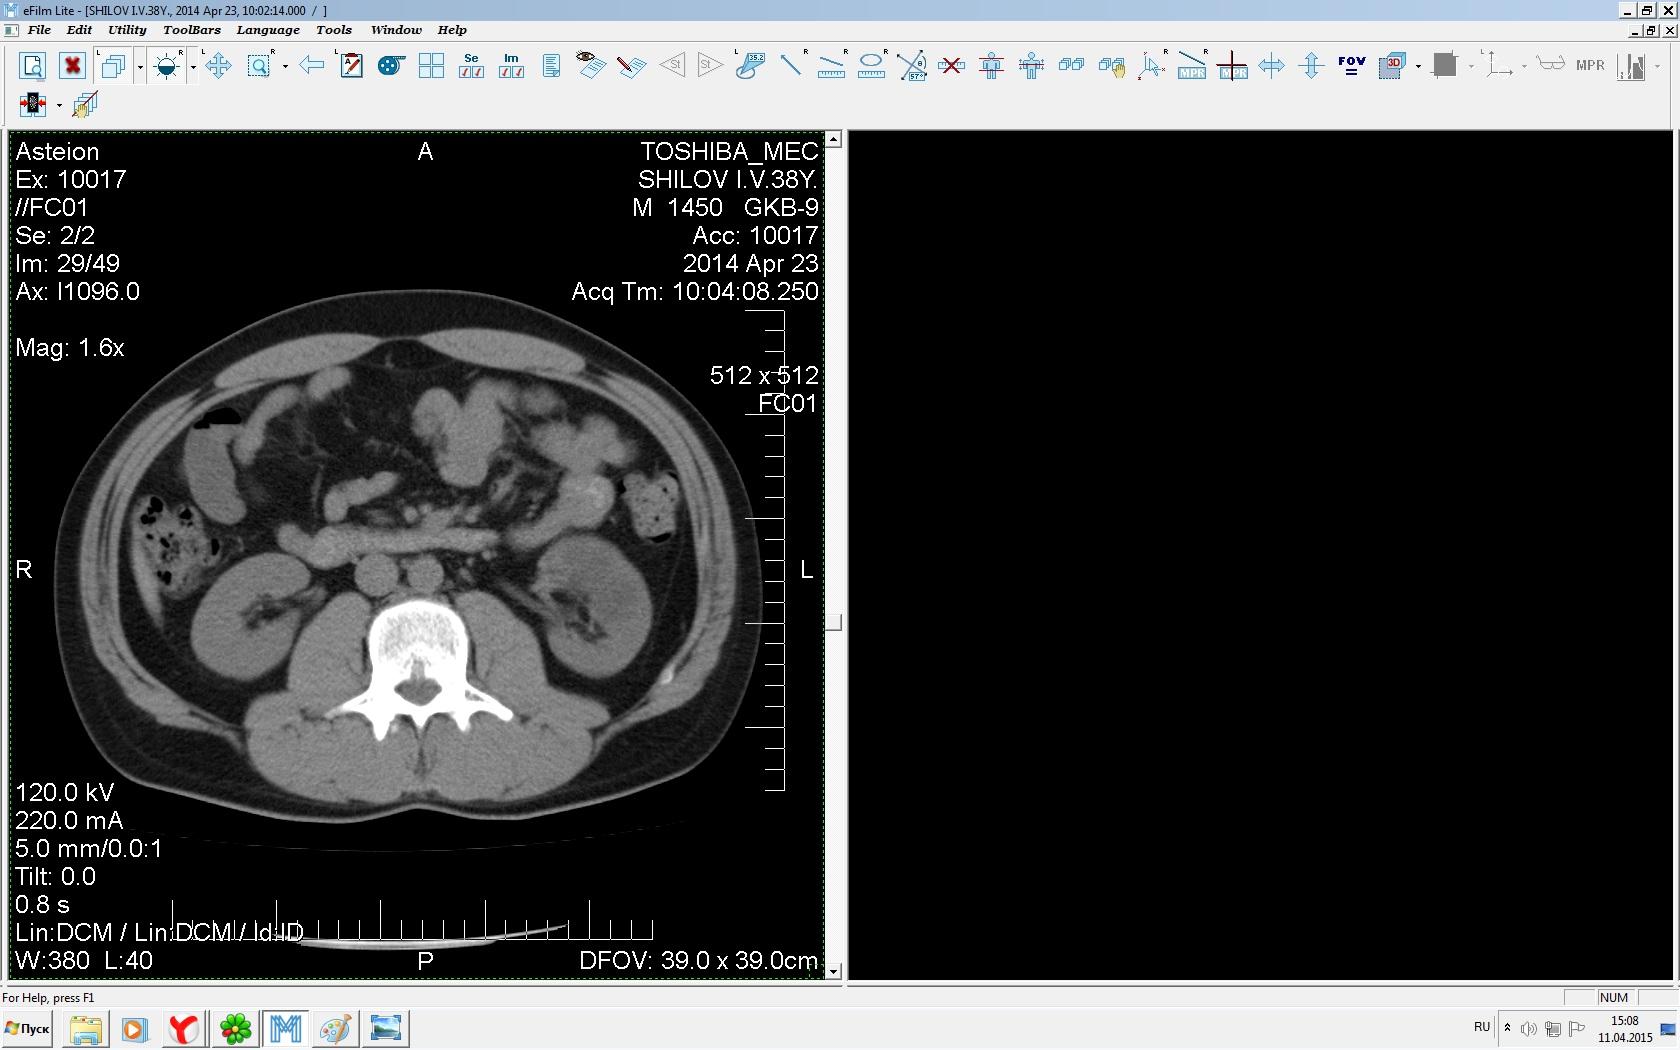

Здравствуйте. У меня киста левой почки. Из заключения: левая почка увеличена, деформирована за счёт наличия в среднем сегменте округлого жидкостного +6, +15 HU образования 66х53 мм, деформирует, поддавливает чаше-лоханочную систему. Сосудистые ножки структурные. В урологии мне сперва предложили лапароскопию, когда я лёг на операцию - изменили на полостную в связи со сложностью. Потом сказали что шансов вырезать кисту без почки практически нет. Даже если кисту удалить чудесным способом, то почка всё равно сложится и не будет работать. В итоге операцию отменили. Скажите, пожалуйста, есть ли современный метод удалить кисту и сохранить почку в моём случае? Томография почки в приложениях. Заранее благодарю.

Эту кисту можно просто пропунктировать, аспирировать и склерозировать - под местной анестезией. Ничего сверхестетственного не определяется по данным КТ. Можете написать мне на почту. aristova-tatyana@mail.ru